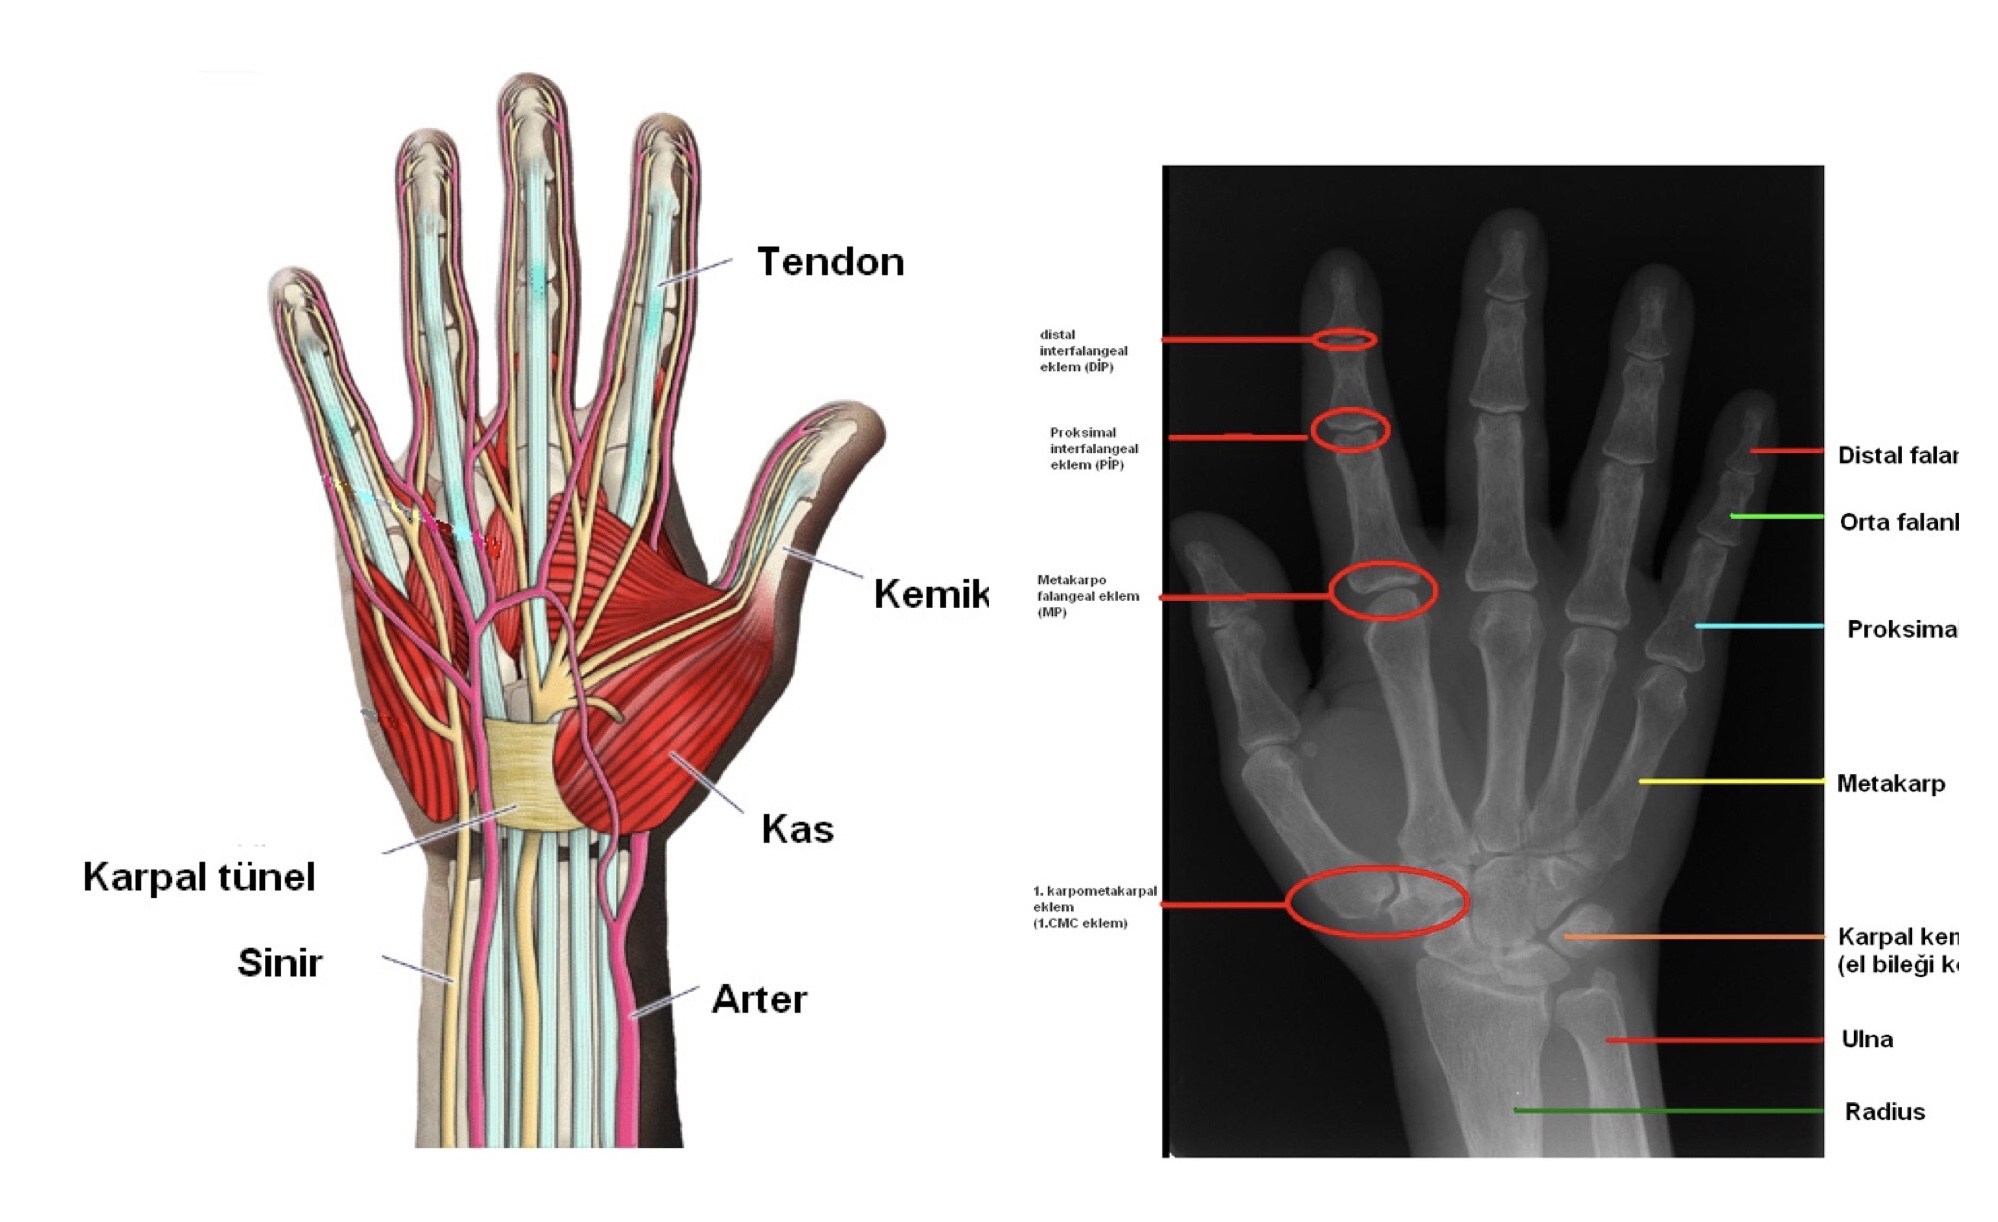

Arama motorunda, yerli ve yabancı araştırma, bilimsel makale ve tez çalışmalarında uyku baloncuğu kavramı aratıldığında söz konusu iddiada kast edilen bir veriye rastlanılmıyor. Bilimsel kaynaklardan insan elinin anatomisi incelendiğinde de “uyku balonculuğu” denilen bir dokunun var olmadığı görülüyor.